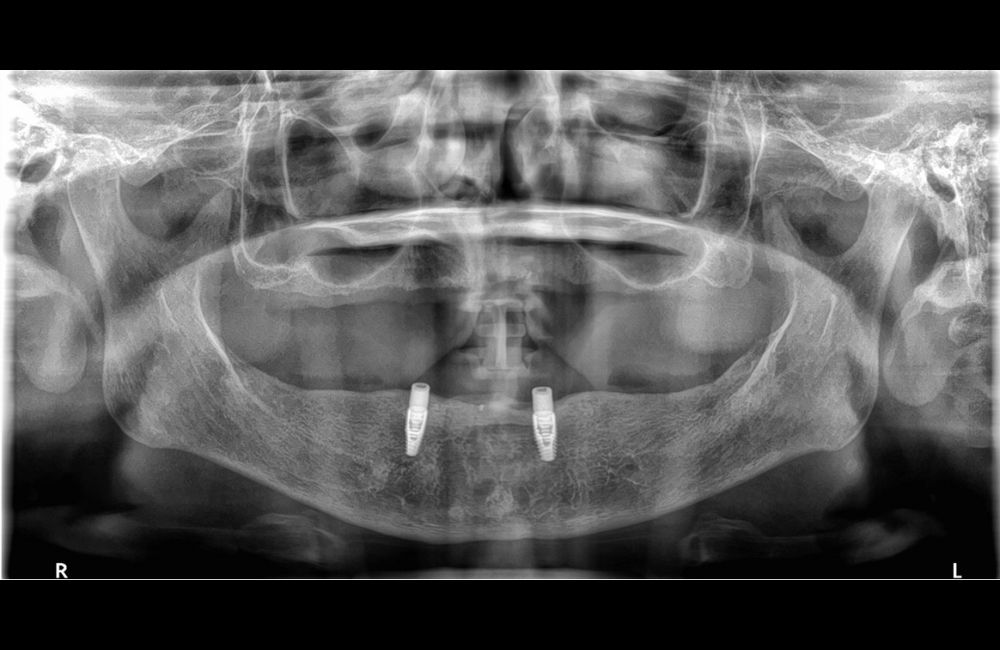

治療後のレントゲン写真

このように、インプラントオーバーデンチャーの治療によって、噛む力や見た目を大きく改善することができました。